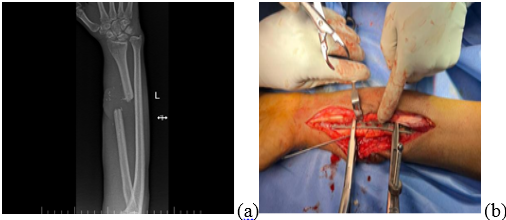

A 52-year-old man was referred to our tertiary care center for a chronic draining wound at the site of a prior open radial shaft fracture. He is a known case of Type 2 diabetes mellitus and is on treatment for the same. The patient initially had a crush injury to the left forearm, which resulted in an absent distal pulse. He was planned for a staged procedure given the Gustilo Type 3C open fracture to achieve an optimal clinical outcome. An external fixator responded by performing a thorough wound debridement, exploration, and bone stabilization. A revascularization procedure was performed by a plastic surgeon on the left forearm, involving primary reconstruction of the left radial and ulnar arteries along with the cephalic vein using a massive saphenous vein graft. Subsequently, a repair of the left median nerve using a cable graft was performed in the initial stage as per damage control orthopedic protocols. Stay sutures were put in, but the defect was not covered. A week later, a groin flap was utilized for coverage of the left forearm. One month after the flap procedure, there was satisfactory flap take-up and no clinical signs of infection; hence, the left groin flap was divided, and the left forearm wound was further debrided and sutured. During this stage, he was planned for definitive fixation of bone; hence, the external fixator was removed. His distal 1/3rd radius fracture with 3 cm bone loss (Fig. 1a and b) was addressed with the volar Henry approach without disturbing the flap extending from the lateral aspect of the radial side to dorsally. He underwent an open reduction internal fixation using a titanium dynamic compression plate, where the 3 cm bone loss was addressed using a fibula strut graft taken from the ipsilateral side (Fig. 2a, b, c).

Figure 1: Pre-operative X-rays of distal 1/3rd radius fracture with 3 cm bone loss.